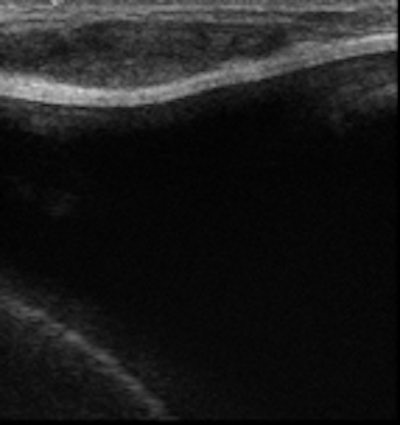

Conventional breast imaging techniques, especially ultrasound, still provide useful information about implants. However, intracapsular rupture, which is frequent but often clinically silent, cannot be easily detected by mammography because of the radiopacity of the implant. The sensitivity of ultrasound is greater if discontinuous echogenic lines within silicone gel ("stepladder sign") are detected. Periprosthetic hyperdensity on mammography and the "snowstorm sign" on ultrasonography are significantly associated with extracapsular rupture.